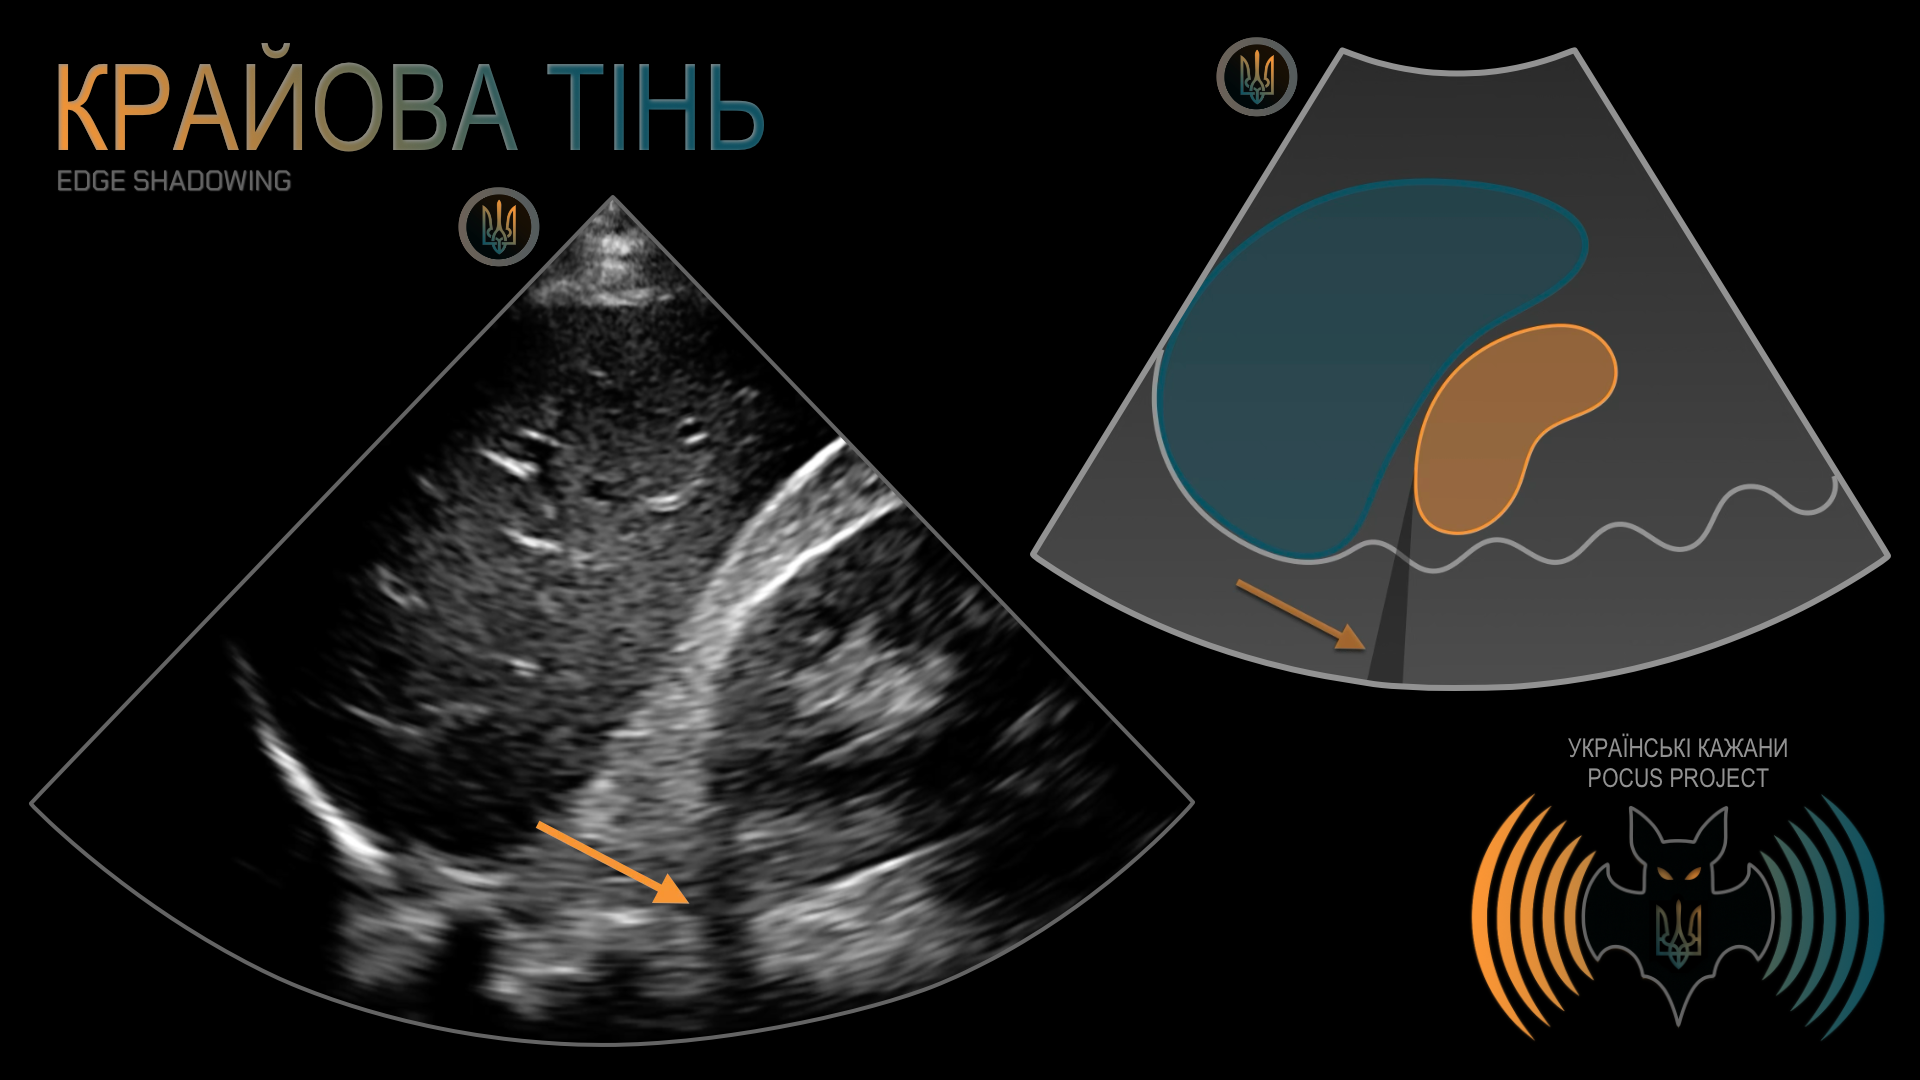

КРАЙОВА ТІНЬ: важливий артефакт, зумовлений рефракцією, тобто відхиленням ультразвукового променя від траєкторії, якою він «мав би» поширюватися. Слід пам’ятати, що УЗ-сигнал не завжди рухається прямолінійно. Таке відхилення найчастіше виникає, коли УЗ-промінь потрапляє на поверхню криволінійного відбивача, наприклад нирки, жовчного міхура або кровоносної судини. Іноді цей артефакт помилково інтерпретують як вільну рідину. У нашому прикладі видно артефактну чорну лінію, що тягнеться прямо від округлого полюса нирки. Звернімо увагу, що вона перетинає кілька анатомічних площин, яких вільна внутрішньочеревна рідина фізично не може досягти. Анатомічного сполучення з черевної порожнини через заочеревинний простір і далі за хребет не існує.